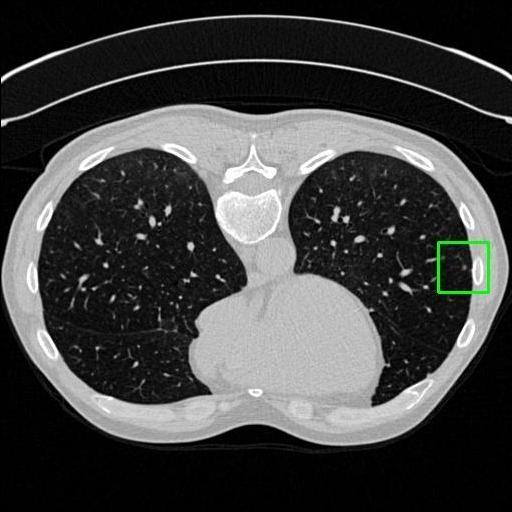

We developed an AI-based system using deep learning models for analyzing lung CT scans to detect and classify pulmonary nodules. We chose the YOLOv11 architecture for its enhanced object detection capability and adapted it specifically for medical imaging, incorporating pixel-level precision and severity classification.

Classification into three severity levels with colored bounding boxes.

Designed a severity classification system that categorizes nodules into null, moderate, and severe using colored bounding boxes, assisting in rapid clinical decision-making.